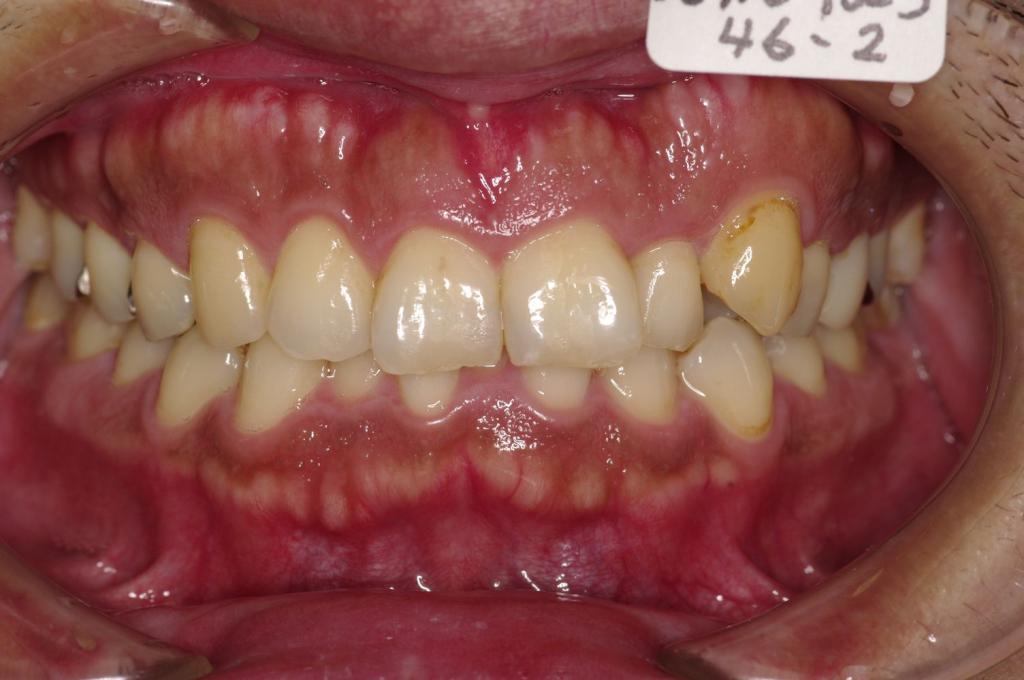

下記の実績データをクリックして頂くと「性別」、「治療開始年齢」、「治療終了年齢」、「治療方法(矯正治療装置写真含む)」、「治療終了までの費用」など、詳細な矯正治療データをご覧頂けます。